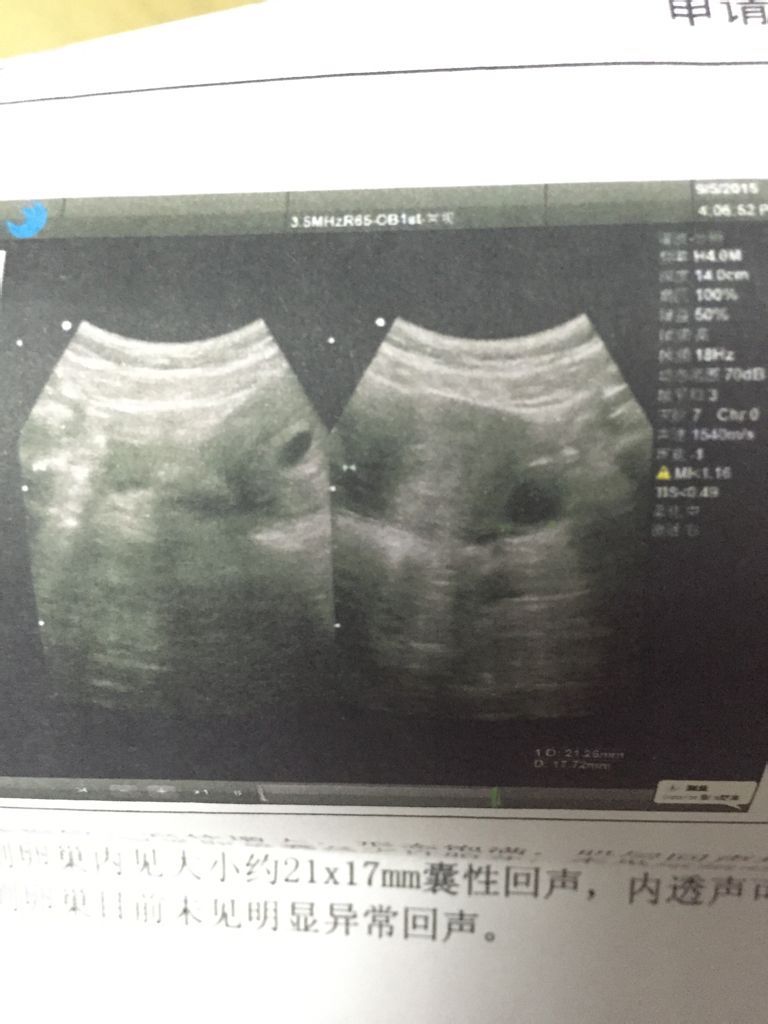

怀孕两个月,孕酮低,上厕所有褐色黑色分泌物,肚子疼,之前有孕吐,犯困,现在没有了 怎么情况 点击展开 匿名用户 2015-09-10 20:30 满意回答 你好,院抓命你的B超和停经月份不符,且孕且肿酮低,有褐色分泌物,是流产的征兆。现在没有胎心,估计胎停育的可能性大。用导建议一周后复查。 ŵ607 2015-09-10 20:45 宝宝知道提示您:回答为网友贡献,仅供参考。 相关问题 怀孕46天早上起床的时候肚子疼上厕所发现有黑色的血,要不要紧? 我六月十八号例假日昨天查hcg值53 96孕酮7 98正常吗?这几天肚子疼,昨天还流出一些褐色分 怀孕8周2天孕酮50降到30有时肚子疼,会不会有问题啊!害怕